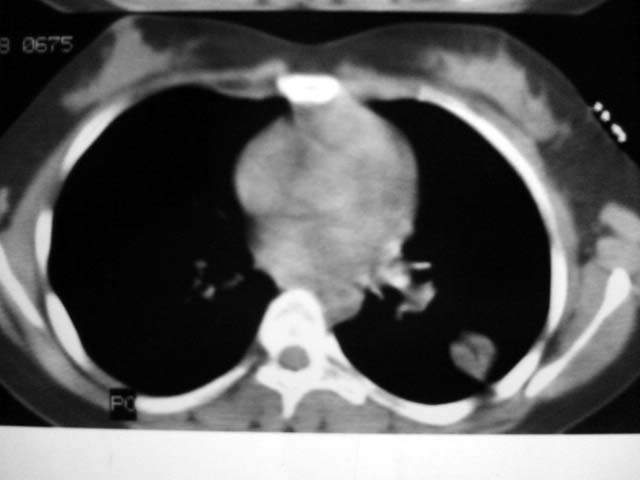

标题: CT12463:女,19岁,炎性假瘤?结核球? [打印本页]

女,19岁,体检时发现。炎性假瘤?结核球?

纵隔窗肿块明显较肺窗小,切粗长毛刺,“倒核桃”征:考虑炎性假瘤

病灶肺纵比较大,边缘平直,周围无卫星灶,考虑炎症。建议抗炎治疗后复查。

病灶片状改变,呈钱币样,周围炎性反应明显,考虑球形肺炎可能性大,球形肺炎与炎性假瘤鉴别的重要一点是,炎性假瘤抗炎治疗不会明显改变。

考虑炎症,抗炎后复查。理由:病变肺窗显示的大小明显大于纵隔窗,提示病变周围为密度偏低的渗出改变。不同于结核球和肿瘤。